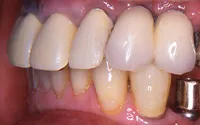

■治療前

■治療後

| 主訴 | 左下の歯が2本なくて咬みにくい 入れ歯はわずらわしいので嫌、金属の被せを白くしたい |

| 治療方法 | インプラント治療+補綴治療 |

| 治療期間 | 約1年 |

| 通院回数等 | 20回位 |

| 費用 | 約150万円 |

| リスク・副作用 | インプラント術後の腫れ・痛み |